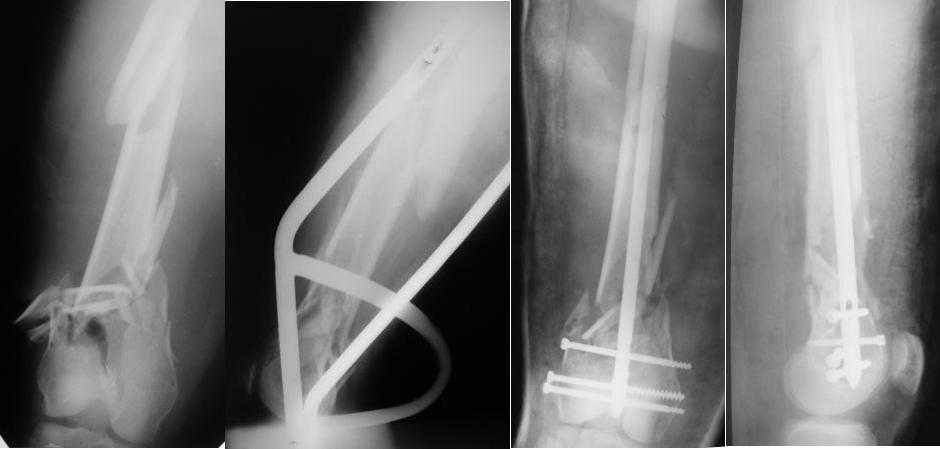

[Ortho] Многооскольчатый перелом бедра

Стержень фирмы НПО ДЕОСТ(г.Пущино-на-оке)